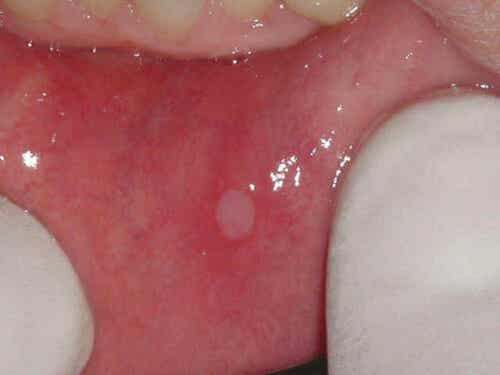

Voedingsdeficiënties zijn ook de oorzaak van aften bij mensen met coeliakie. Met name een tekort aan vitamine B12 en foliumzuur zijn de directe boosdoeners. Vergeet hierbij niet dat het mondslijmvlies deel uitmaakt van hetzelfde slijmvlies dat zich uitstrekt tot in de darm. Geen wonder dus dat een reactie in het onderste deel van het spijsverteringsstelsel zich ook in het bovenste deel manifesteert.

Aften in de mond zijn zweertjes die vanzelf genezen. Ze duren meestal een week en het genezingsproces laat geen blijvende sporen na. Ze zijn echter wel vervelend en maken kauwen pijnlijk. Daarom veranderen ze vaak het dieet van mensen die toch al aan strenge beperkingen onderworpen zijn.